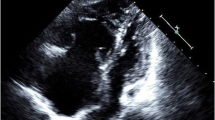

Echocardiography does not directly diagnose PE but is an important tool to measure severity and prognosis of the patient. Echocardiography evaluates biventricular systolic function, pulmonary pressure, and the presence of a patent foramen ovale (PFO). The most common measurements obtained from echocardiography are the right ventricle (RV)/ left ventricle (LV) ratio to evaluate for RV dilatation (normal ≤ 1); the RV fractional area change (normal ≥ 35%); and the tricuspid annular plane systolic excursion or TAPSE (normal < 15 mm) to evaluate RV systolic function. McConnell’s sign (RV akinesia in the mid free wall with hyperkinetic function at the apex) is a distinct echocardiographic finding in patients with moderate to severe PE [24]. The hypokinesis of the RV is independent predictor of early death in normotensive PE patients [25]. The presence of a PFO in PE patients has been associated with an increased risk of stroke [26]. In acute PE, we recommend performing the baseline echocardiogram including the injection of agitated normal saline to rule out a PFO. In patients presenting with a paradoxical embolism it is recommended to perform a pulmonary embolectomy and the closure of the PFO. However, there is no consensus about management of a PFO in acute PE patients without neurologic symptoms.